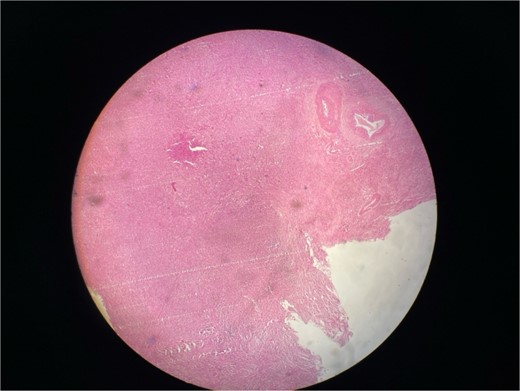

Gross examination revealed mass along GB 5 × 2 × 1 cm and attached 5 × 4 × 2 cm liver. Cut section of GB mucosa is velvety and fundus is thickened measuring 1.2 cm. Histopathology report revealed polygonal eosinophilic cells with granular cytoplasm strongly positive for periodic acid-Schiff (PAS) (Figs 3 and 4). These cells also contain vesicular small centrally located nucleus which appears in clusters or sheets and infiltrated diffusely within the surrounding structures suggesting of Granular cell tumor. All the margins were negative for tumor. Liver was unremarkable, so were the regional lymph nodes. Immuno-histochemistry confirmed CD 68 positivity and negative for SOX10, CK, SMA, desmin, Ki-67 favoring the neural origin of the tumor further enhancing the diagnosis (Figs 5 and 6).

Microscopic picture shows polygonal eosinophilic cells arranged in clusters and diffusely infiltrates the surrounding cell.

Microscopically these tumors contain granular eosinophilic cytoplasm with vesicular nucleus where granules are positive for periodic-acid Schiff’ staining. They appear in cluster or sheets. They infiltrate surrounding tissue diffusely separated by thin connective tissue. Mitoses are rare. No necrosis is present. Reactive atypia of the overlying epithelium and metaplastic pyloric gland may mimic carcinoma [7, 9, 10]